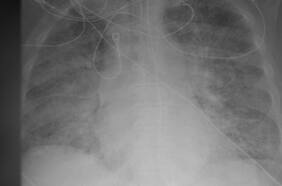

La radiografía del paciente se ve casi completamente blanca, lo que se conoce como opacidad pulmonar. Mientras que en pacientes con la vacuna, se observa una gran cantidad de espacio negro, lo que muestra que pudieron inhalar una cantidad de oxígeno en su mayoría saludable.

Radiografía muestran cómo pulmones de persona no vacunada infectada con Covid se llenan con el virus mientras que lo de una vacunada están libre de la enfermedad